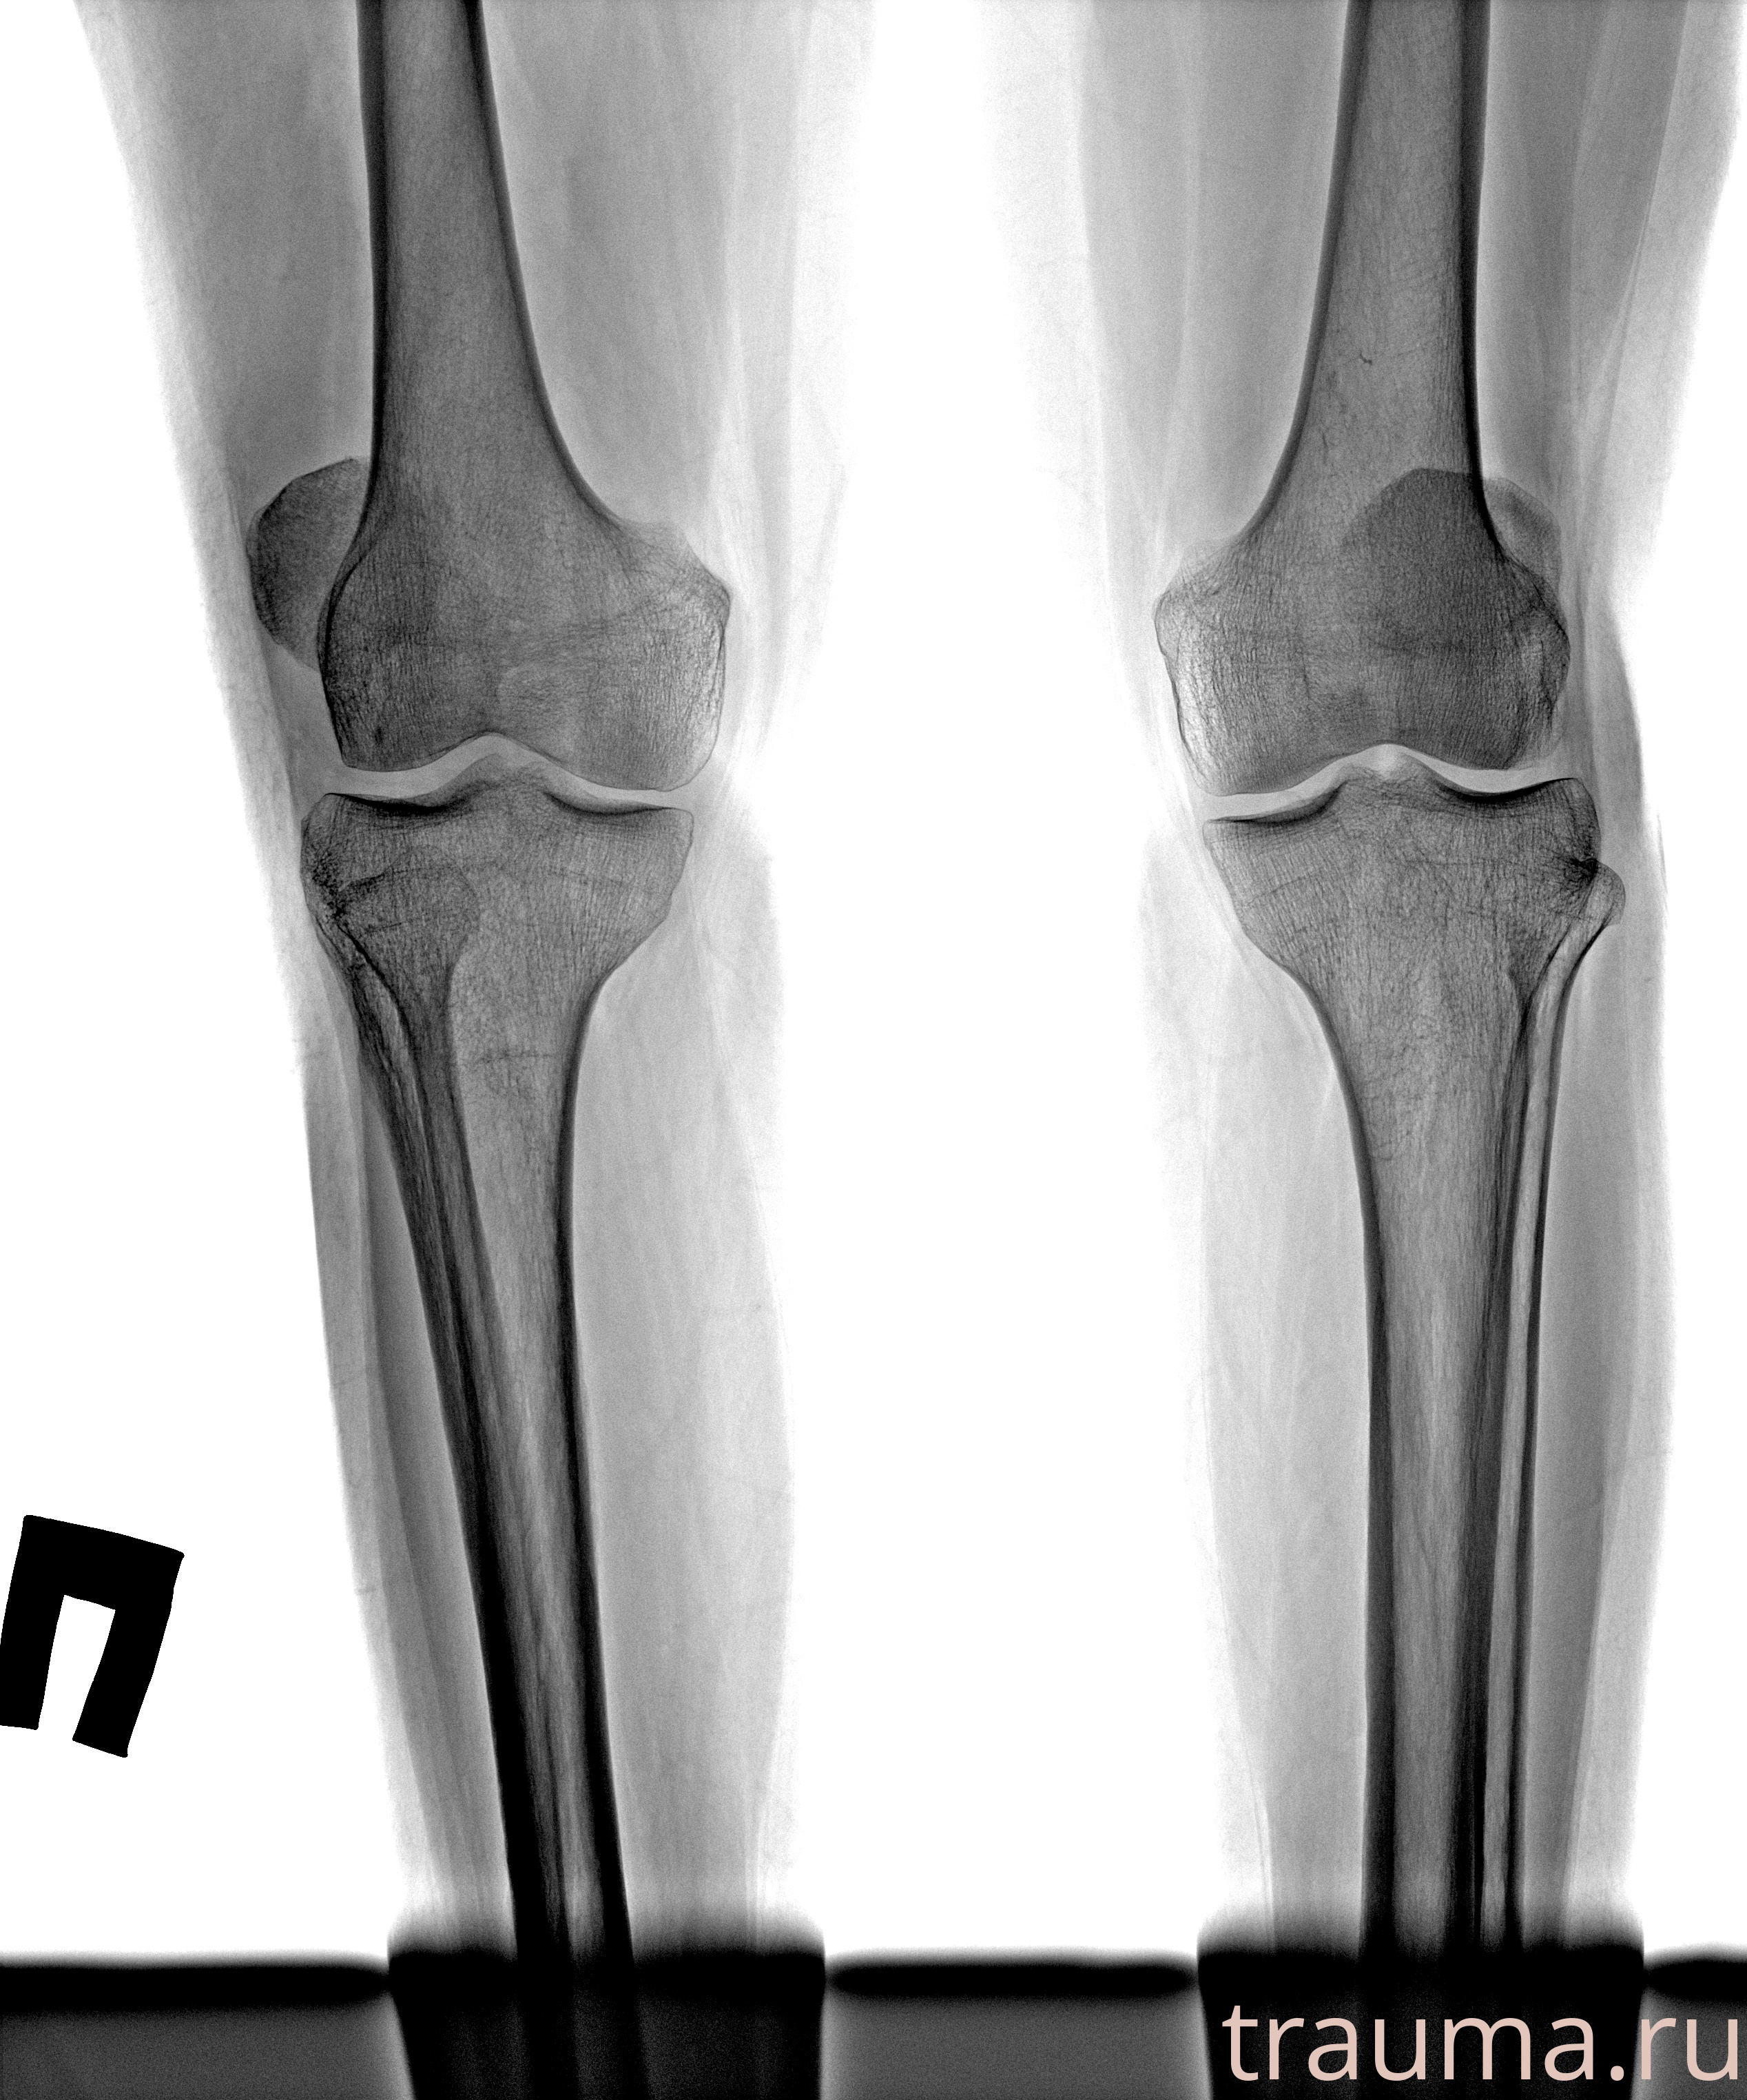

Рентгенограммы

Рентген на дому: по вашему адресу приезжает врач-рентгенолог, травматолог-ортопед с мобильным рентгеновским аппаратом, проводит диагностику травмы или заболевания, делает необходимые рентгенограммы, дает рекомендации по дальнейшему лечению. Получить качественные снимки в домашних условиях возможно благодаря уникальной методике, разработанной МосРентген Центром для института  Склифосовского